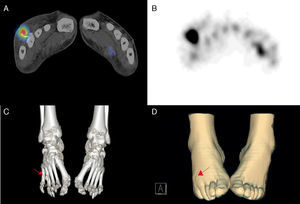

Varón de 45 años, sin antecedentes de interés, con dolor y tumefacción en el dorso del pie derecho (fig. 1D), con exudado purulento en la zona interdigital del 4.° y 5.° dedo, de 6 meses de evolución, y con cultivos repetidamente negativos, que no mejoraba con tratamiento antibiótico intensivo. Las imágenes radiológicas fueron no concluyentes, por lo que acude a nuestro servicio para la realización de una gammagrafía1 con leucocitos marcados con 99mTc-HMPAO (fig. 1A y B), evidenciándose un aumento de captación del trazador en el 4.° metatarsiano a las 3h postinyección del radiotrazador2. El estudio se completó con la adquisición de una tomografía por emisión de fotón único/tomografía computarizada y reconstrucción 3D (3D-SPECT/TC) que permitió localizar el proceso infeccioso en partes blandas del dorso del pie, relacionadas con un cuerpo extraño, en el tercio distal de 4.° metatarsiano (fig. 1C) desconocido hasta la fecha. Tras la exéresis quirúrgica de este, la evolución fue excelente en pocas semanas.

SPECT/TC tras la administración iv de leucocitos autólogos marcados con 20mCi de 99mTc-HMPAO. Imagen de fusión SPECT/TC (A) e imagen SPECT (B) en las que se observa depósito patológico de captación a nivel del 4.° metatarsiano del pie derecho. Reconstrucción 3D con ventana ósea (C) que permite correlación del hallazgo gammagráfico con la presencia de cuerpo extraño (flecha) que impronta sobre la superficie de la piel (D).

La imagen híbrida SPECT/TC con leucocitos autólogos marcados con 99mTc-HMPAO y reconstrucción 3D es una herramienta de alta precisión en el diagnóstico no invasivo de los procesos infecciosos asociados a cuerpos extraños no visibles con técnicas de imagen morfológicas.